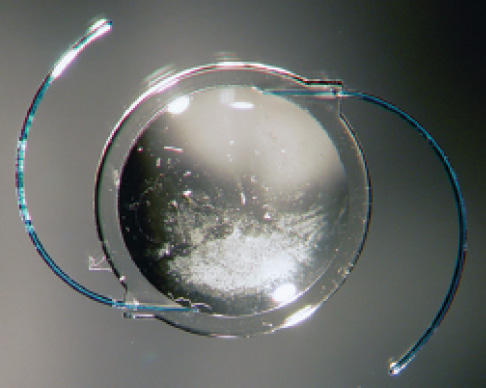

Figure 1. A hydrophilic acrylic IOL explanted after pars plana vitrectomy, exhibiting localized calcification on the anterior optic surface and subsurface.

Liliana Werner, MD, PhD: We have analyzed different hydrophilic acrylic IOLs explanted because of a localized form of calcification on the anterior surface and subsurface of the optic, in an area generally limited by the capsulorhexis opening (Figure 1). Many cases were related to posterior lamellar keratoplasty techniques, such as Descemet-stripping endothelial keratoplasty (also known as DSEK) or Descemet-stripping automated endothelial keratoplasty (also known as DSAEK).1 Retrospective studies on those types of cases demonstrated that the rate of this complication could be as high as 9.7%.2 It appears that, in the instances of calcification, repeated intracameral air or gas injections were performed.

More recently, we have analyzed at least 30 other cases in which the same pattern of calcification occurred after procedures in the posterior segment, such as pars plana vitrectomy with gas or silicone oil, or after intravitreal injections of anti-VEGF agents. We do not know the rate of this complication after procedures in the posterior segment yet, as there are still no clinical studies done to verify it.

Calcification occurs in the area where the optic contacts the aqueous humor. Therefore, the key in these eyes implanted with hydrophilic acrylic IOLs—of various manufacturers and designs—may be a chronic disruption of the blood-aqueous barrier with a change in the aqueous humor occurring after repeated intraocular procedures. It is possible that the nature of the tamponade and the direct contact between the tamponade with the IOL do not represent the main factors.